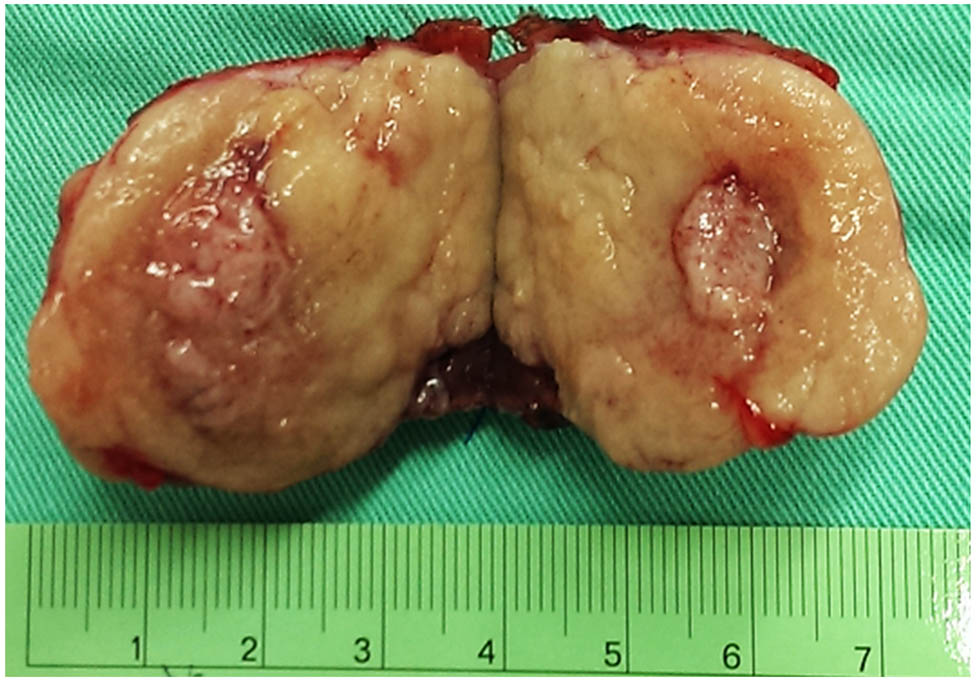

Given the uncertain nature of the tumors, we first excised the exophytic renal tumor and checked the tumor nature with intraoperative frozen section for tissue proof. As there was no evidence of malignancy of the frozen section, we then performed enucleation of the main endophytic tumor instead of radical nephrectomy (Figure 2). Microscopic finding revealed the tumor having uniform and hyperchromatic nuclei, growing in a gyriform and ribbon-like pattern without a well-formed capsule (Figure 3). Immunohistologically, the tumor cells expressed neuroendocrine markers including CK, vimentin, neuron-specific enolase, synaptophysin and chromogranin. The final diagnosis is a well-differentiated, grade 1, neuroendocrine tumor (NET), also known as a carcinoid tumor.

The specimen of the main renal tumor.